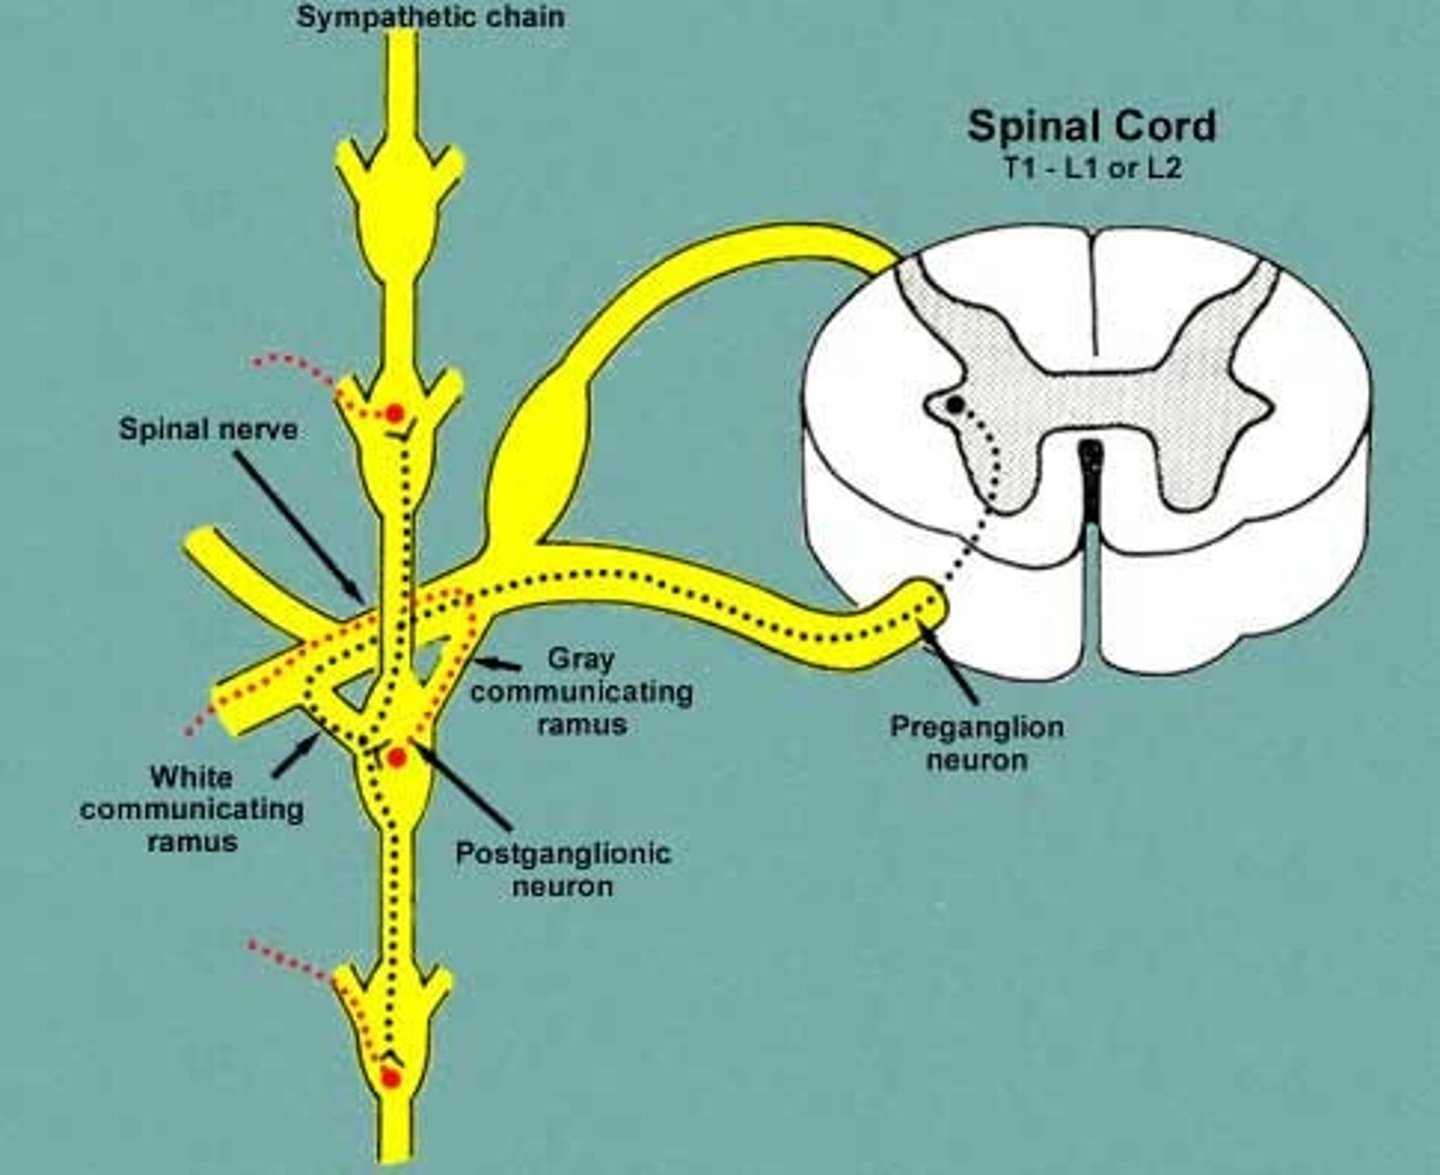

sympathetic trunk/chain ganglia

Runs along vertebrae, part of the sympathetic nervous system, keeps whole body in sync

White rami communicans

contain myelinated preganglionic fibers traveling to sympathetic trunk ganglia

gray rami communicans

contain unmyelinated postganglionic fibers traveling from ganglia to peripheral structures